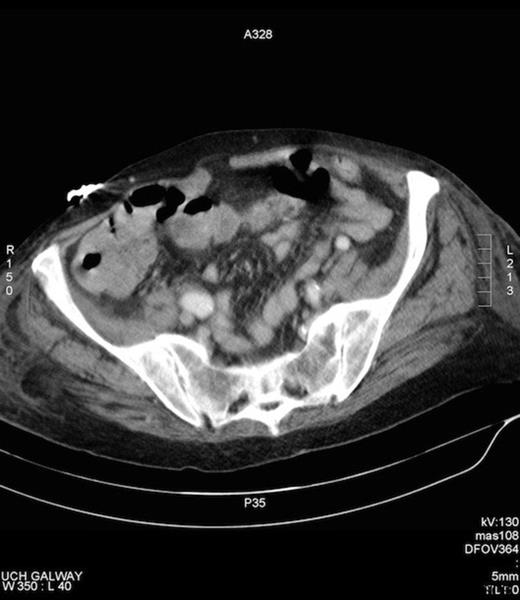

She denied bowel symptoms. Examinations in the SOPD revealed an erythematous, tender swelling in the right groin, with an opening exuding malodorous fluid that had caused marked skin excoriation. On abdominal examination she was tender to palpation in the right groin and guarding and rebound tenderness were absent in the right iliac fossa. There was no clinical evidence of sepsis. A colocutaneous fistula was suspected clinically, when over several days the discharge became faeculent. A CT fistulogram showed a fistulous tract communicating with the caecum and the peritoneal cavity (Figures 1 and 2). She subsequently underwent an elective laparotomy for a planned right hemicolectomy, on a presumptive diagnosis of either a caecal tumour or inflammatory process.

CT fistulogram post injection of contrast via the groin opening. Contrast can be seen to fill the caecum, confirming the presence of a fistula.